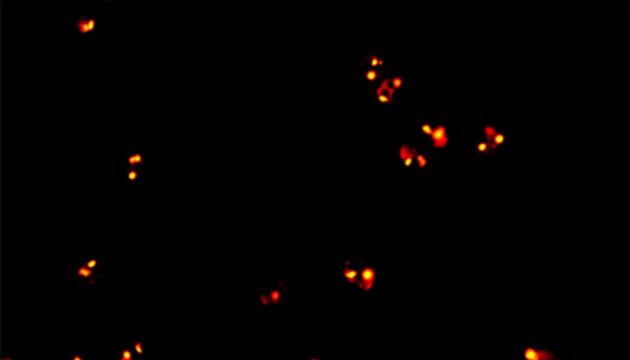

CTC檢測用于上皮腫瘤,如胃腸癌、皮膚癌等。檢測分四步:富集、CD45染白細(xì)胞、CK染CTC、DAPI染核。有DAPI、CK熒光且無CD45熒光,大核細(xì)胞為CTC;有DAPI、CD45熒光為白細(xì)胞。

CTC循環(huán)腫瘤細(xì)胞檢測中的難點

CTC檢測面臨儀器通用性差、多色熒光閱片繁瑣及高靈敏度成像難三大難點。新技術(shù)如微流控芯片有望取代專用儀器,提升富集效率。使用電動熒光顯微鏡搭配微流控,可更高效率進行CTC成像和閱片。另外為滿足高靈敏度成像需求,建議配置優(yōu)質(zhì)LED光源、高效濾光片、半復(fù)消色差或以上物鏡及高靈敏度相機。

MF43-N用于CTC檢測